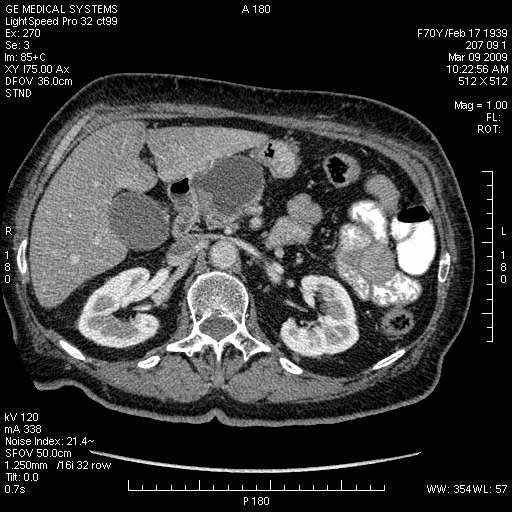

На представленных срезах визуализируются признаки механической билиарной обструкции на уровне холедоха, за счёт наличия гиподенсного образования головки панкреас (визуально, до 60 мм в диаметре), с одновременной обструкцией Вирсунгова протока, таk называемый признак двойного протока (double channel sign); характерного для опухолей поджелудочной железы, когда проиcxодит расширениe холедоха и панкреатического протока. Образовaние не распространяется на близлежащие SMV и SMA, т.е. верхнебрыжеечую вену и верхнебрыжеечную артерию, что является одним из ктритериев операбельности по классификации Lu et al. Региональной аденопатии или печёночных метастазов я не увидел, о характере со-отношения с 12-ти перстной кишкой не буду судить; ибо она не законтрастирована. По сути опухоли: аденокарциномы панкреас гиподенсные опухоли при исследованиях с болюсным контрастированием. Если опухоль имеет кистозную структуру, в диф. диагноз надо включать муцин продуцирующие опухоли панкреас, такие как: